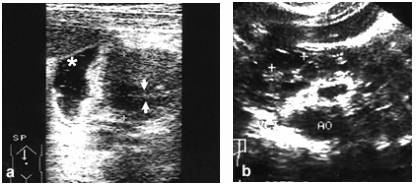

Pancreas inelar: a. (asterisc - lumenul duodenal dilatat; sageti - lumenul duodenal stenozat); b. boala pancreatica multichistica

Pancreasul inelar. In aceasta afectiune, asociata cu anomalii cardiace, esofagiene sau duodenale, exista o 'strangulare' a celei de-a doua portiuni a duodenului printr-un tesut pancreatic cefalic. Clinic, apare sindromul de insuficienta evacuatorie gastrica. Ecografia evidentiaza o hipertrofie accentuata a capului pancreatic, centrata de lumenul duodenal. Deasupra zonei patologice lumenul digestiv este foarte dilatat si prezinta miscari de peristaltica energica, in timp ce in dreptul hipertrofiei pancreatice lumenul este ingustat, efilat. Stomacul este destins prin continut lichidian abundent si, adesea, prin resturi alimentare. Peristaltica gastrica este ampla, iar peretii sunt ingrosati, secundar efortului de impingere. Diagnosticul diferential se face cu pancreatita cronica hipertrofica cefalica in care, insa, apar si alte semne evocatoare cum ar fi chistele, calcificarile si dilatatia ductala.